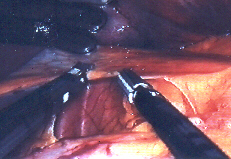

Es beruht darauf, daß in der Nabelgrube, also hernach nicht mehr sichtbar, lediglich nur ein 10 mm- Trokar (Hülse zum Einbringen der Instrumente) plaziert werden muß. Durch diesen wird, unter Sicht mit einer ganz normalen 10-mm-Optik die Praeparation des Ductus cysticus (Gallenblasenganges) und der Arteria cystica (Gallenblasenarterie) mit den Microinstrumenten im Calot´schen Dreieck vorgenommen.

2mmop.jpg (26106 Byte)Operation mit 2 mm Instrumenten

Nachdem diese Strukturen identifiziert und isoliert sind, wird daraufhin das Clippen der beiden Lumina unter der Kontrolle der xyphoidal (am Unterrand des Brustbeins) eingeführten 2-mm- Optik mit dem am Nabel eingeführten 10-mm-Clip-Instrument durchgeführt. Das Auslösen der Gallenblase aus dem Leberbett geschieht dann wieder mit der konventionellen 10-mm Optik unter Zuhilfenahme des Koagulationsstroms der 2-mm-Schere.

Danach wird wiederum die Optik umgesetzt, also die 2-mm-Optik rechts xyphoidal eingebracht und unter Sicht mit dieser Optik die Gallenblase am Nabel exhairiert (herausgezogen).